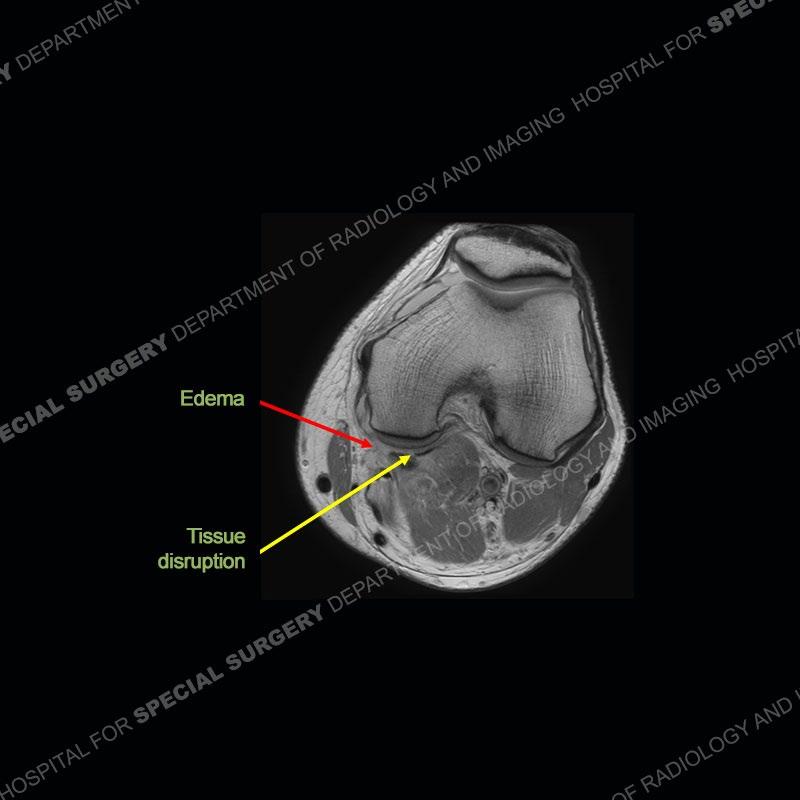

The radiographs show degenerative change of the medial compartment and a varus knee, but they are not germane to this case. No acute bony injury is present. The MRI shows edema of the posterior medial knee/soft tissue and a focal area of a partially disrupted low signal structure. The details are kept at a minimum in the findings of this case on purpose.

Diagnosis: Partial Disruption Medial Head Gastrocnemius (MHG)

The findings were kept purposefully vague as identifying the structures early on takes away a lot of the diagnosis. An uncommon entity and one of which we do not see a lot. Enthesopathic changes and tendinosis are seen as are distal MHG injuries, but proximal tears are rarely present. This case highlights a number of points. One, it almost always comes down to anatomy. Perhaps not a structure we normally spend too much time on, except save for diagnosing a Baker’s cyst, but knowing where this structure and all structures exist in all three planes is imperative. Second, when you think you are making a “call” or finding that you have never made before, step back and think is this just the abnormal presentation of a common pathology. That situation arises much more frequently. Third, if you look at it once, twice, and probably a third time and are confident in your odd or very rare diagnosis, stick to your guns. Especially, when it comes down to anatomic structures, the proof will be in the images.

Fourth, use all imaging planes and different pulse sequences to make your diagnosis. The edema highlighted in this case can be seen as the obscuration of fat on the PD images but is much easier to perceive as the high signal on the IR pulse sequences. The actual disruption of the MHG myotendinous junction is only able to be seen on the axial images. On the sagittal and coronal images, we get a sense something is wrong but hard to be exact. Lastly, when you look at a study and something just seems off (as I would say the sagittal and coronal images do with that dark band of tissue posteriorly), listen to yourself and go through the study slowly and meticulously. Most of the time you will find you were right, and something indeed is present.